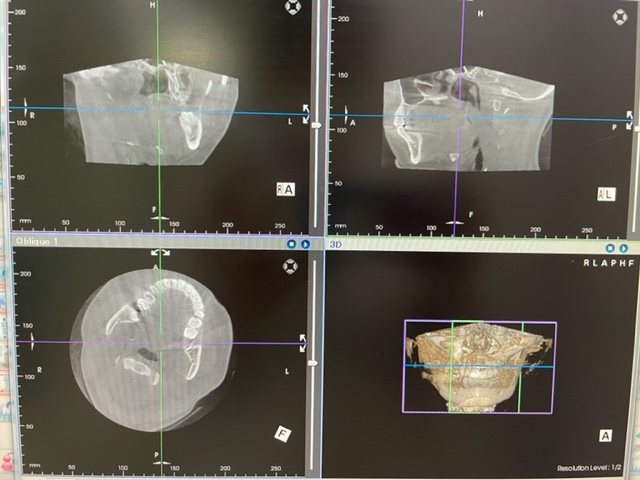

パノラマレントゲンとCTを撮って診断してもらいました。

その結果、顎の骨が少し溶かされてきてるので早めに抜いたほうがいい。とのことで